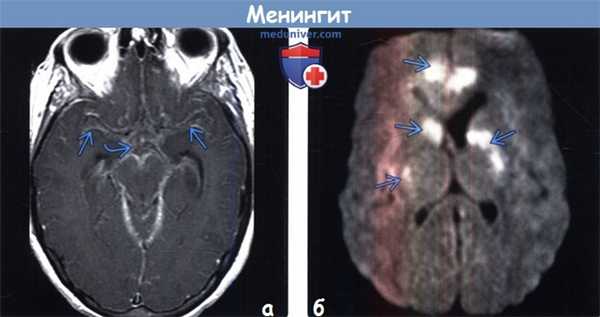

(а) МРТ, постконтрастное Т1-ВИ, аксиальный срез: у пациента с бластомикозом в базальных цистернах и сильвиевых бороздах отмечается распространенное лептоменингеальное контрастирование, что обусловлено менингитом.

(б) МРТ, ДВИ, аксиальный срез: у этого же пациента определяется мультифокальное повышение интенсивности сигнала, что обусловлено острыми инфарктами. Ишемия может являться результатом спазма/окклюзии артерий или истинного артериита. ДВИ является крайне значимой методикой для оценки осложнений менингита.